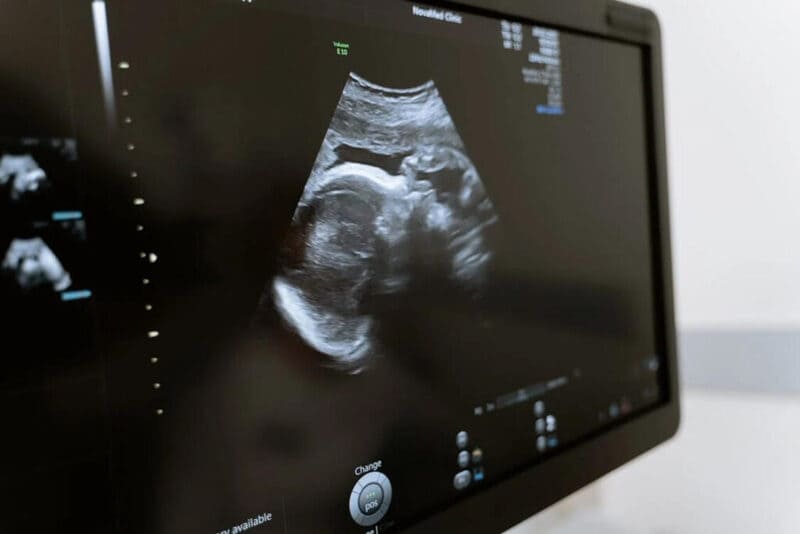

O Supremo Tribunal Federal (STF) começou a julgar na madrugada desta sexta-feira (22) a ação que tenta descriminalizar o aborto feito por mulheres com até 12 semanas de gestação. A votação foi suspensa por um pedido do ministro Luís Roberto Barroso, e a análise será feita de forma presencial.

Há, também, três exceções atuais à regra. O aborto é permitido até a 12ª semana de gestação se:

- a gravidez é decorrente de um estupro;

- o feto é anencefálico, ou seja, não terá condições de desenvolver um cérebro (e de sobreviver fora do útero);

- há risco de vida para a gestante.